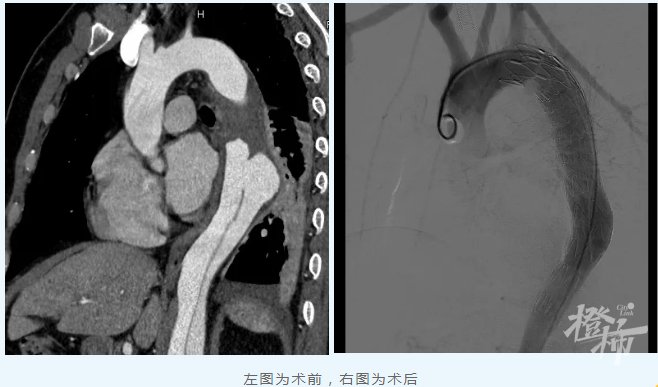

浙江省立同德医院血管外科医护团队第一时间为其进行了充分的病情评估和细致的沟通,并立即收治入院密切监护治疗。经过一段时间积极监护治疗、充分评估和完善相关准备后,血管外科严金副主任医师团队DSA(血管造影术)下在周先生主动脉腔内精准置入覆膜支架隔绝修复夹层破口。术后第一天,周先生就能正常下床活动,第四天康复出院。

文章插图